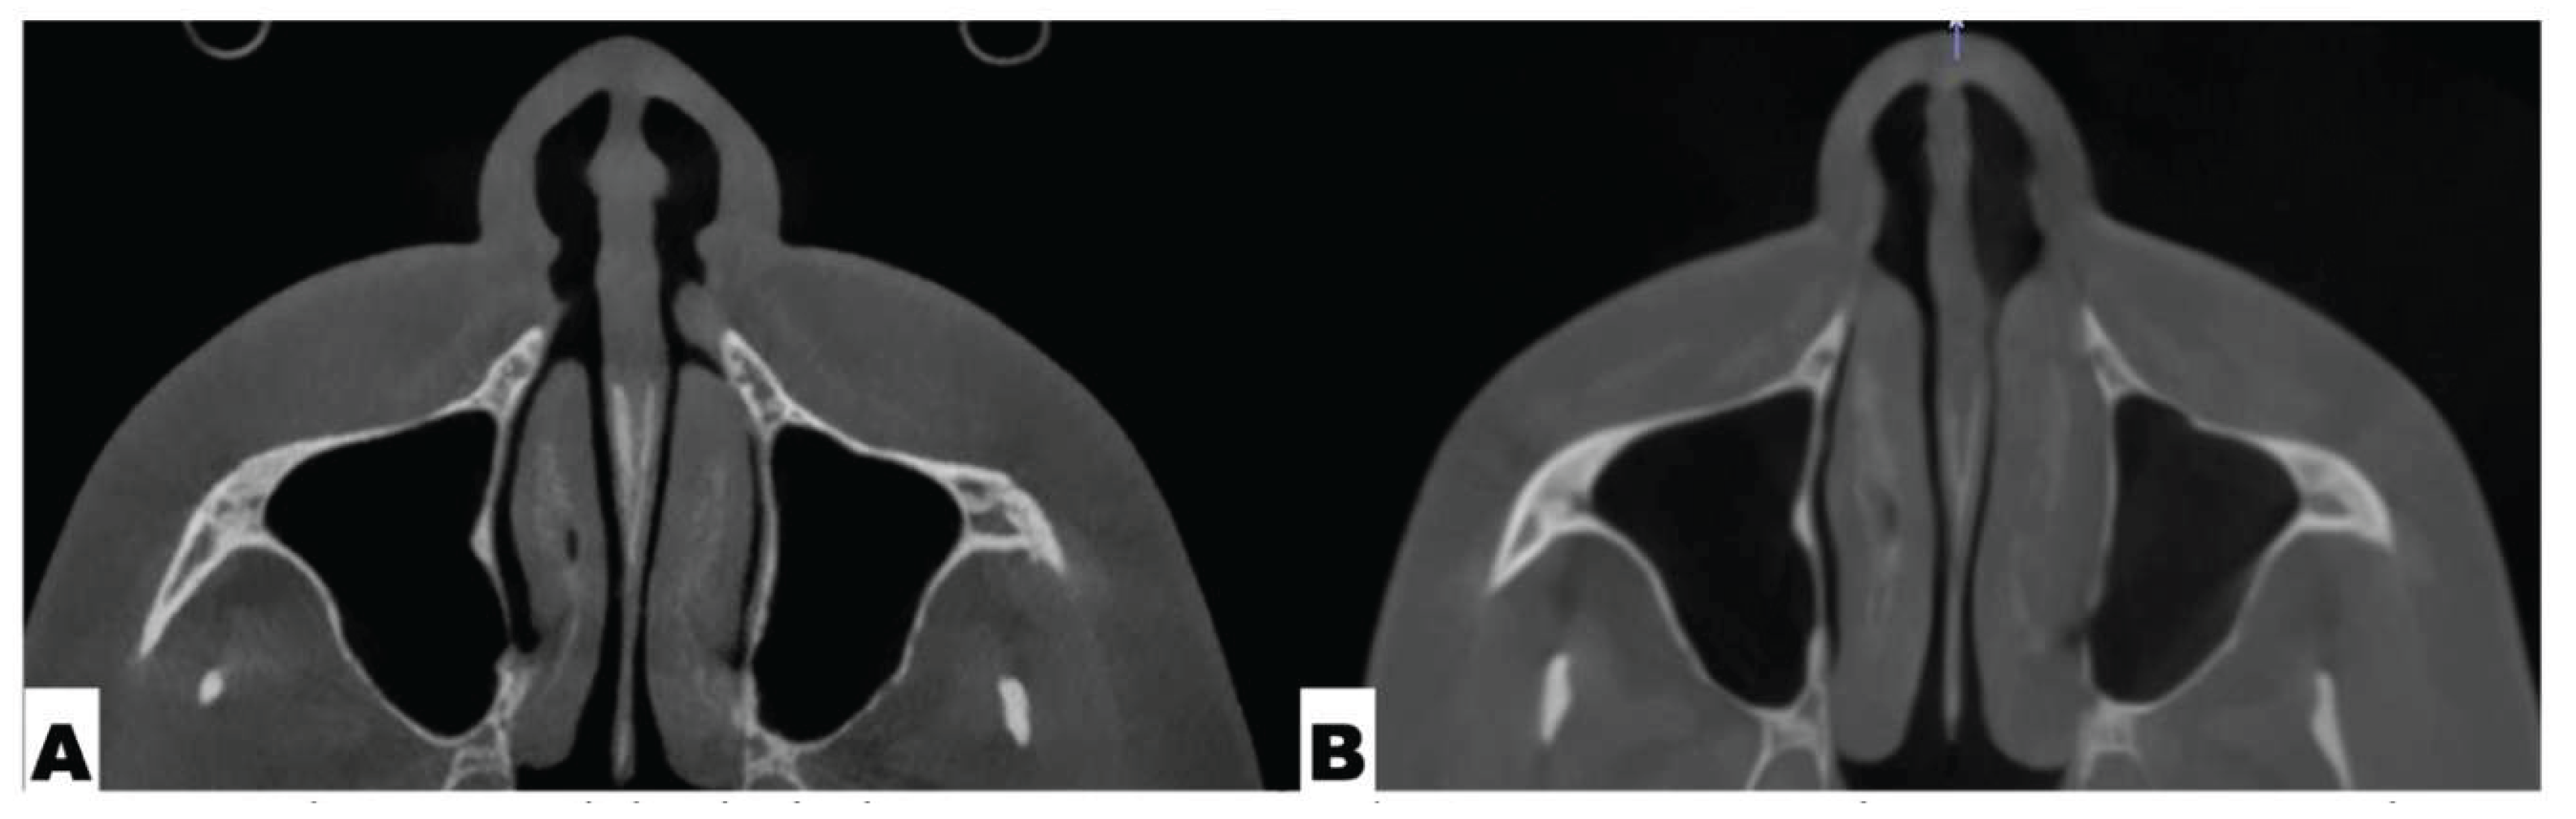

Background: While mini-screw-assisted rapid palatal expansion (MARPE) is effective for correcting maxillary transverse deficiency in adults, perimaxillary suture disarticulation—particularly at the pterygomaxillary junction—can be inconsistent. This study evaluates skeletal and dentoalveolar outcomes of a novel 3D-guided midpalatal piezocorticotomy-assisted MARPE protocol, focusing on expansion symmetry and pre-existing asymmetries. Methods: Three adult patients were retrospectively analyzed after treatment with 3D-guided midpalatal piezocorticotomy-assisted MARPE expansion and one with non-guided midpapalatal piezocorticotomy and MARPE expansion. Surgical guides were digitally designed using CBCT data to align with the nasal septum orientation in multiple planes. Perimaxillary suture disarticulation was measured pre- and post-expansion, and dentoalveolar changes were evaluated. Post-expansion asymmetries were addressed using directly printed aligners. Results: Complete midpalatal suture separation (mean 8.48 mm), involving both anterior and posterior nasal spine regions, was achieved in one patient. Bilateral pterygomaxillary disarticulation averaged 1.06–1.23 mm, resulting in forward–outward rotation of the nasomaxillary complex. Additional separation occurred at the frontonasal (2.03 mm) and vomeromaxillary (1–2 mm) sutures, with no significant changes in orbital or peri-orbital sutures. One patient presented with pre-existing dentoalveolar asymmetry, which intensified the perceived post-expansion imbalance but was successfully corrected with directly printed aligners. In the second case, 5.6 mm of suture separation resulted in a limited lateral nasal width increase (<1.5 mm), while maxillary base expansion exceeded 6 mm. A significant canine plane cant (1.2 mm) and divergent axial inclinations of the maxillary central incisors relative to the palatal plane were also observed. In the second case, a non-impactful palatal bone fracture with asymmetric displacement of the left palatine fragment was documented. After 16 months of aligner therapy, all cases exhibited favorable remodeling of the palatal structures, midpalatal suture, and alveolar processes, accompanied by improved dental alignment, occlusal plane symmetry, and mandibular dentoalveolar adaptation. The dento-alveolar expansion achieved in the third case over the course of 16 months of treatment was approximated at 4 mm. The fourth case showed consistent improvement with direct printed aligners after MARPE midpalatal diasrticulation of 11 mm after experiencing minor bone fracture. Conclusions: Human skulls exhibit considerable variability between the left and right sides, which can influence spatial balance. Pre-existing cranial asymmetries appear to be the primary contributors to asymmetry following MARPE treatment. Careful evaluation of dentoalveolar discrepancies and axial tooth inclinations is essential for preventing and managing potential asymmetric dental arch outcomes during the post-expansion phase. Although peri-maxillary bone fractures are relatively uncommon, their occurrence is influenced by multiple factors. Adjunctive techniques, such as 3D-guided midpalatal piezocorticotomy, show promise in significantly lowering the risk of intra-expansion peri-maxillary fractures.